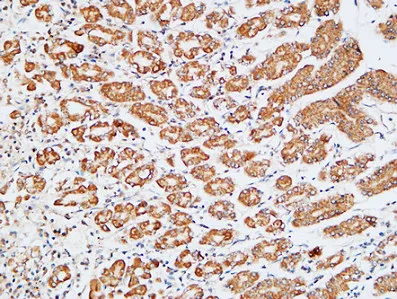

HDC Rabbit Polyclonal Antibody

Cat: APRab11956

Size1:50μl Price1:$118

Size2:100μl Price2:$220

Size3:500μl Price3:$980

Size2:100μl Price2:$220

Size3:500μl Price3:$980